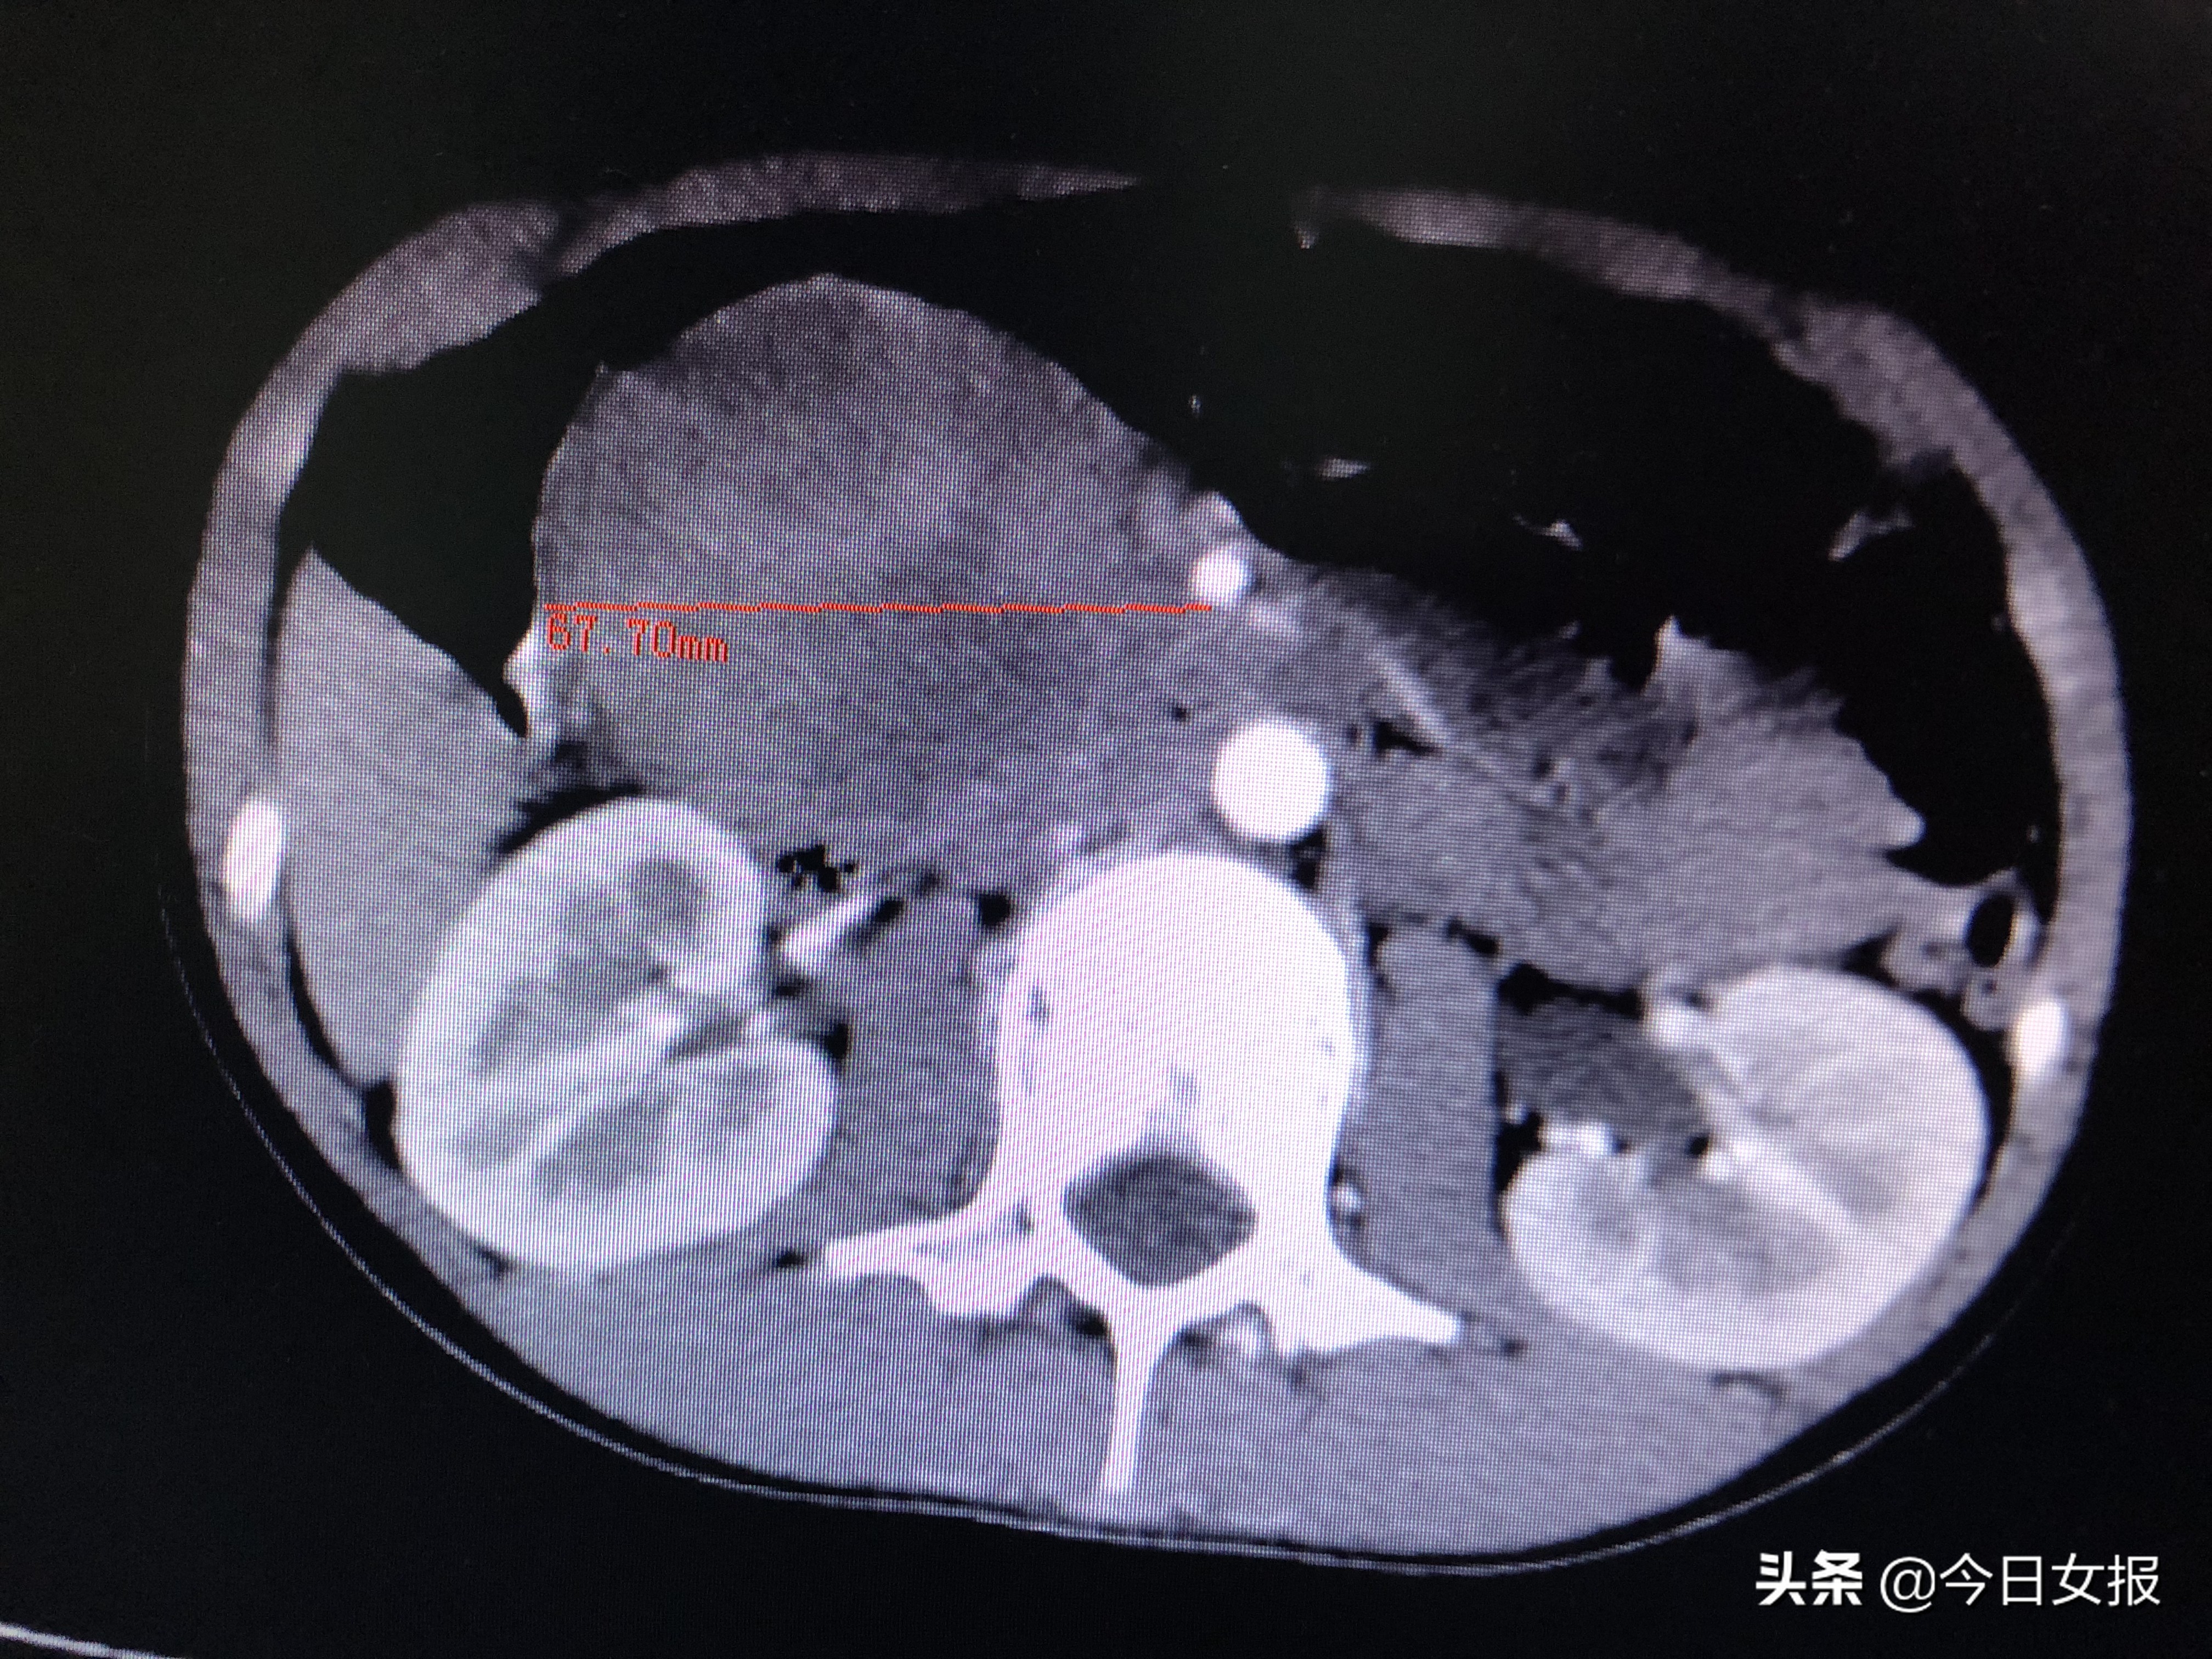

10岁的婷婷(化名)来自湖南省永州市冷水滩区,2019年4月12日上午,她在课间操时与同学一起踢毽子,被一名男同学不小心踢到肚子。不久后,婷婷感到上腹部剧烈疼痛,随后出现恶心、呕吐的情况,吃不了东西,连喝水都吐。家长闻讯后将她送到当地医院,做了腹部超声、CT等检查后被告知,婷婷的胰头部位长了个“很大的东西”,建议前往长沙进一步治疗。

4月17日晚上7时许,在完善相关检查进一步明确病情并排除手术禁忌后,由蒋波、陈梅福、成伟等专家组成的手术团队为婷婷施行急诊全麻下腹腔镜胰十二指肠切除术。术中发现,肿瘤压迫十二指肠、结肠,且出血后粘连严重,腹腔镜下分离难度极大;同时,肿瘤与肠系膜上静脉、肠系膜上动脉、门静脉等重要血管紧邻,一不小心就容易损伤这些大血管,手术风险和难度不言而喻。所幸在专家团队的高超技艺和谨慎操作下,手术于次日凌晨3时许顺利结束,切下的肿瘤达67×61×50mm3,病理检查证实为“胰头实性假乳头状瘤并出血”。